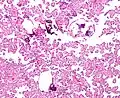

Histopathology

The tumor is neuroectodermal in origin and similar in structure to a normal choroid plexus. They may be created by epithelial cells of the choroid plexus. Papillary fronds lined by bland columnar epithelium are visible under the microscope. Normal absences include mitotic activity, nuclear pleomorphism, and necrosis.[10] Tumors have positive immunohistochemistry for cytokeratin, vimentin, podoplanin, and S-100.[11] Up to 20% of choroid plexus papilloma patients may test positive for glial fibrillary acidic protein (GFAP).[12] Studies have found that fourth ventricle cancers express more S100 than lateral ventricle tumors, and older patients (over 20 years) express more GFAP and transthyretin than younger patients.[13] Some individuals with choroid plexus papilloma have germline TP53 gene mutations, according to genetic analyses.[14] These cancers rarely exhibit nuclear p53 protein positivity. Aicardi syndrome, hypomelanosis of Ito, and 9p duplication are syndromic correlations of choroid plexus papilloma.

Micrograph of a choroid plexus papilloma. H&E stain.